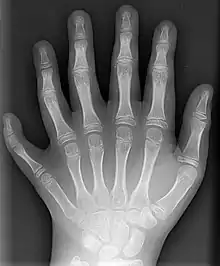

Radiographie d'une main polydactyle postaxiale

Définie comme l’existence des doigts supplémentaires du côté de l'ulna ou d’orteils du côté de la fibula (donc du côté du petit doigt). Elle peut être complète : présence d'un doigt bien formé ou plus rudimentaire.